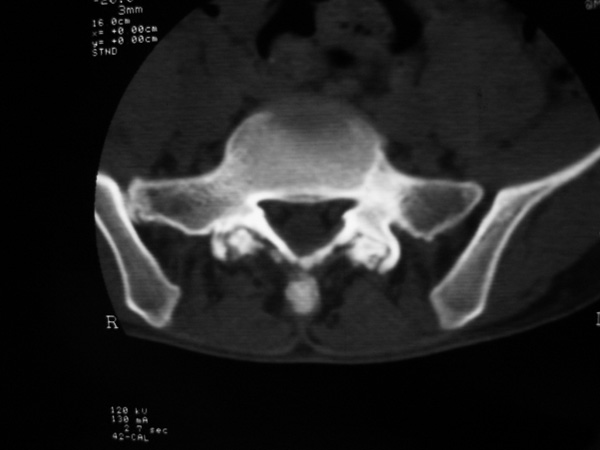

以下是引用w_jianhua在2007-3-8 11:14:00的发言:[br]椎小关节及右侧骶髂关节关节面毛糙,间隙不规则狭窄,骨皮质增生硬化,支持强直性脊柱炎,并椎间盘膨出

以下是引用fumaogui在2007-3-8 8:40:00的发言:[br]腰椎椎间关节增生硬化,关节间隙变窄,右侧骶髂关节间隙变窄,关节面硬化[br]考虑强直性脊柱炎.建议结合化验查:c--反应蛋白和类风湿因子.